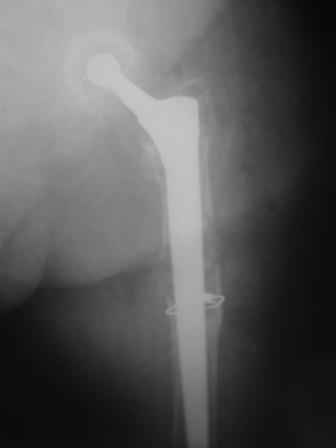

Female, rheumatoid, THA in 2003, car accident in 2006, failed plating. Nailing in Oct 2007. The nail is solid with hollow proximal part where the stem is docked. Last images are in 1 year after

nailing.